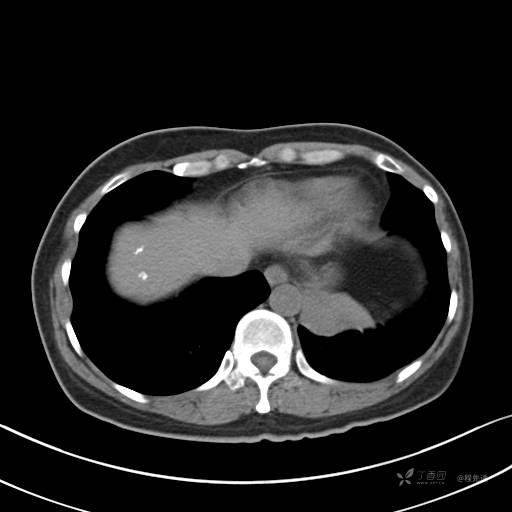

增强静脉期

静脉期CT值约84HU

CT值:平扫:31HU,动脉期:74HU,静脉期:84HU